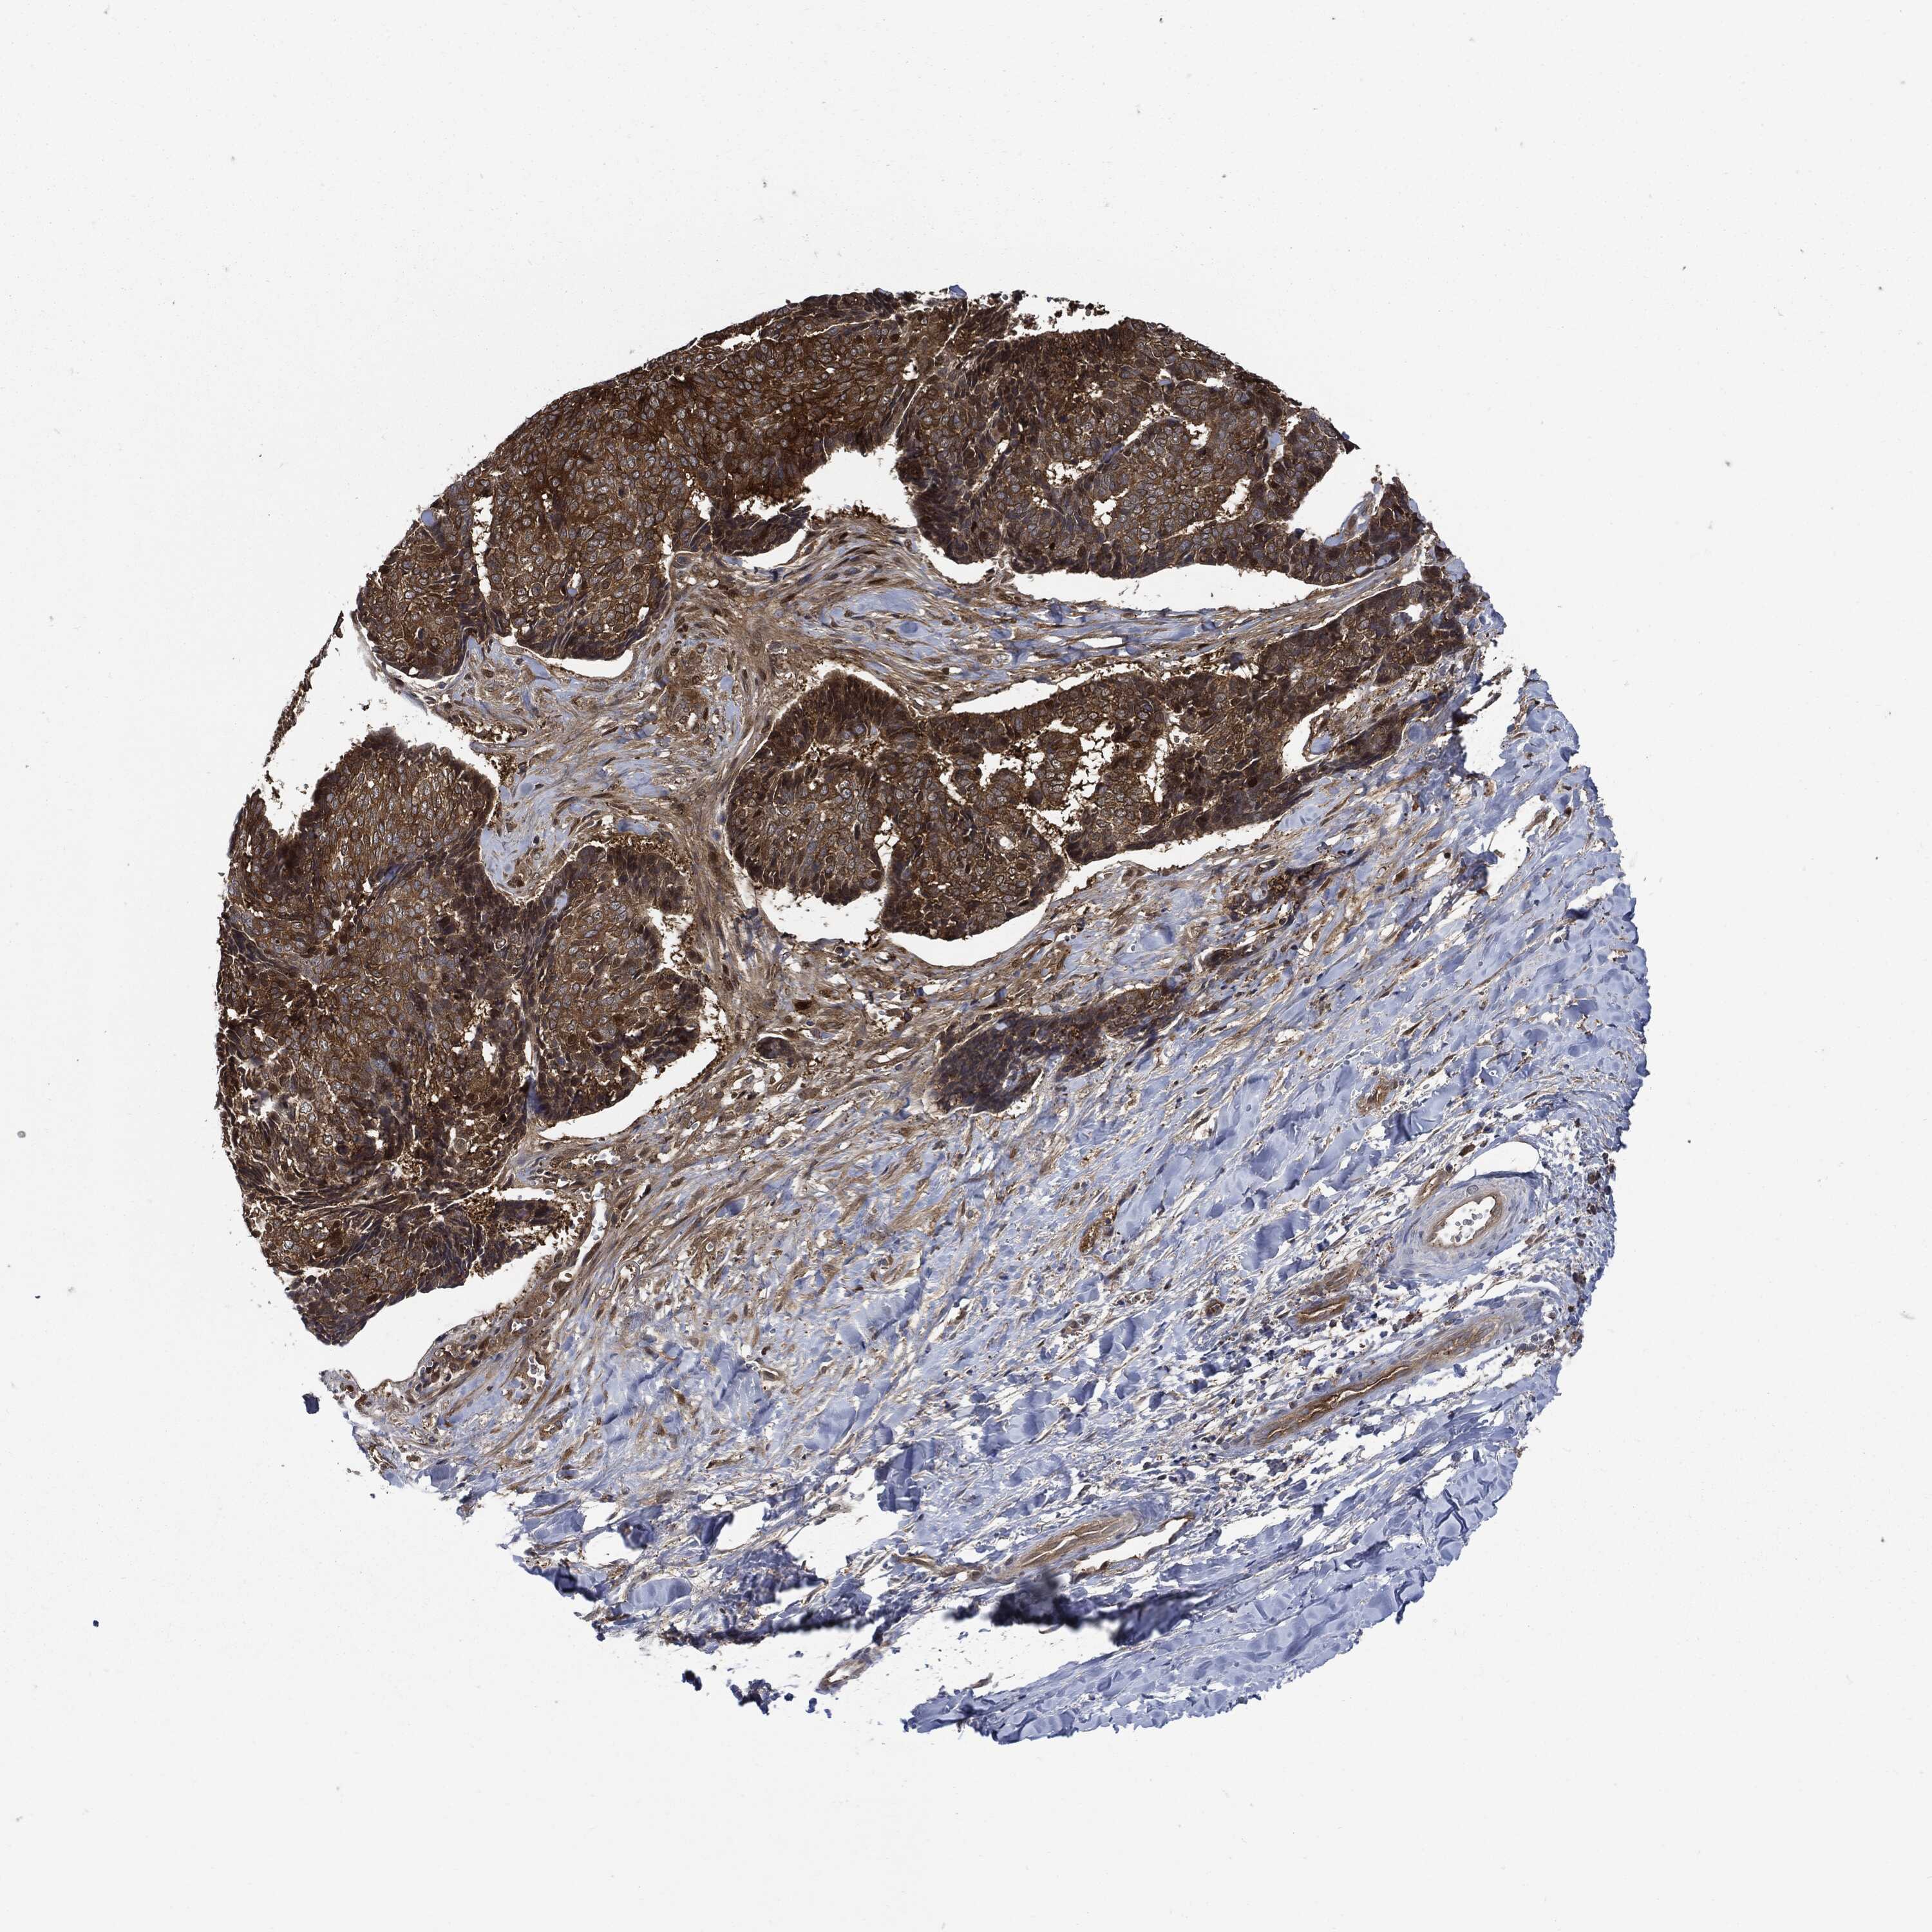

CANCER SKIN CANCER Show tissue menu

Basal cell and squamous cell cancer

SKIN CANCER - Protein expressioni

A mouse-over function shows sample information and annotation data. Click on an image to view it in a full screen mode. Samples can be filtered based on level of antibody staining by selecting one or several of the following categories: high, medium, low and not detected. The assay and annotation is described here.

Each image is clickable and will lead to virtual microscopy that enables deeper exploration of all samples and also displays staining intensity scores, fraction scores and subcellular localization as well as patient and tissue information for each sample.

Squamous cell carcinoma, NOS